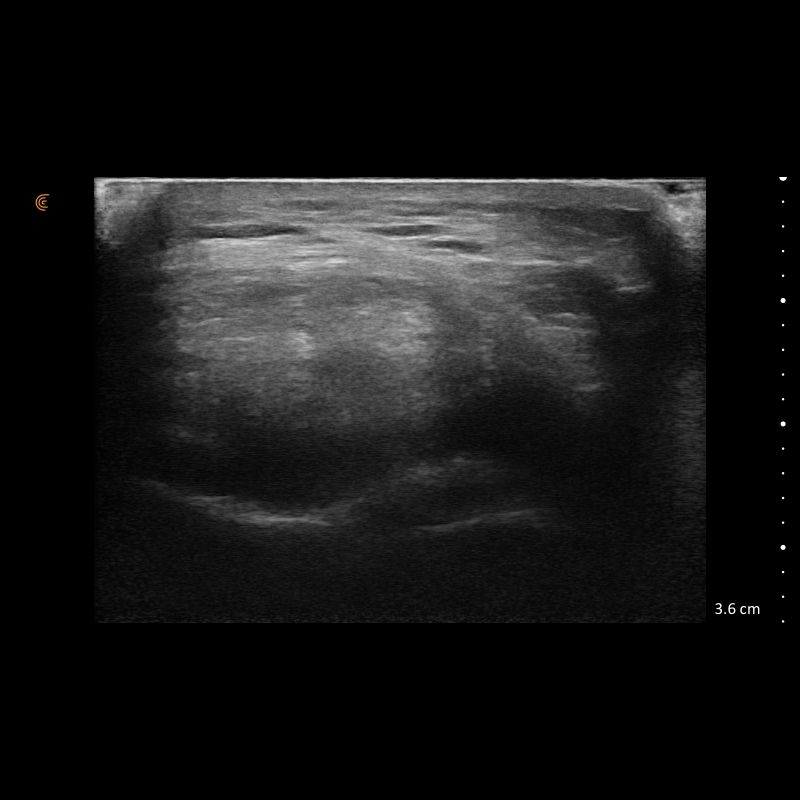

Images from the C7V HD3